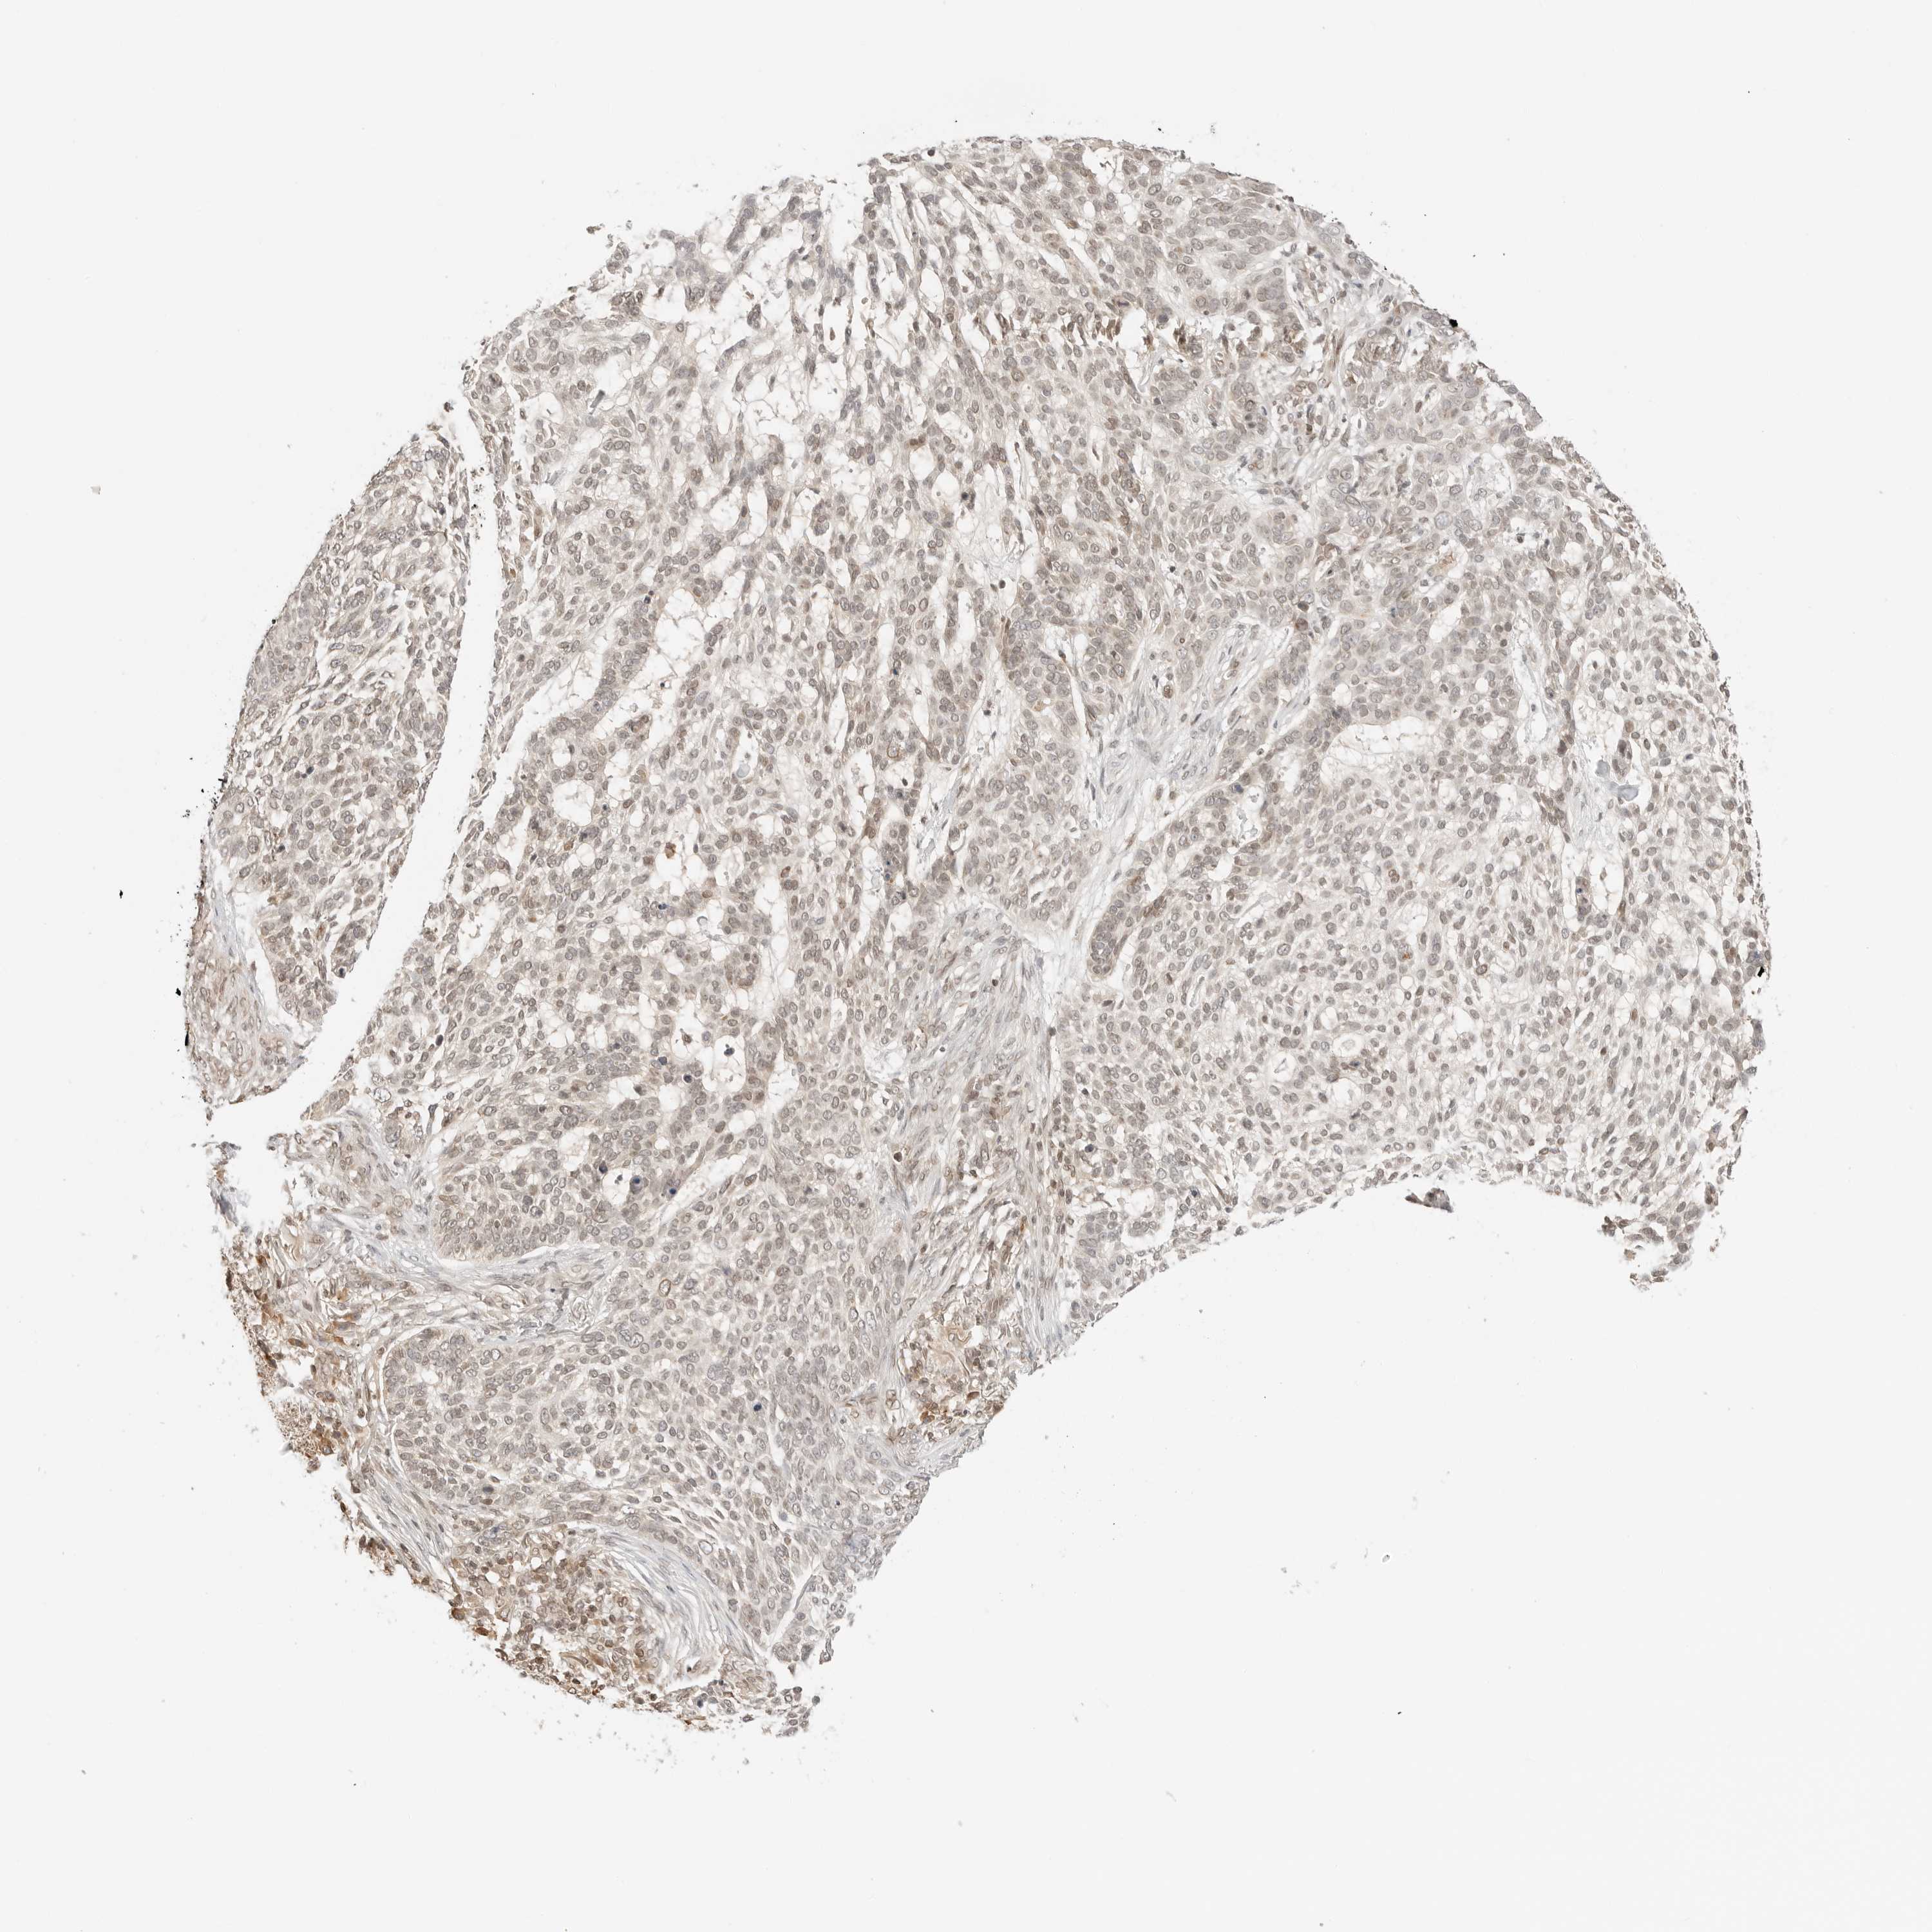

SKIN CANCER - Protein expressioni

A mouse-over function shows sample information and annotation data. Click on an image to view it in a full screen mode. Samples can be filtered based on level of antibody staining by selecting one or several of the following categories: high, medium, low and not detected. The assay and annotation is described here.

Antibody stainingi

Antibody staining in the annotated cell types in the current human tissue is reported as not detected, low, medium, or high, based on conventional immunohistochemistry profiling in selected tissues. This score is based on the combination of the staining intensity and fraction of stained cells.

Each image is clickable and will lead to virtual microscopy that enables deeper exploration of all samples and also displays staining intensity scores, fraction scores and subcellular localization as well as patient and tissue information for each sample.

Antibody HPA026762

Staining

Medium

Intensity

Quantity

Location

Squamous cell carcinoma, NOS